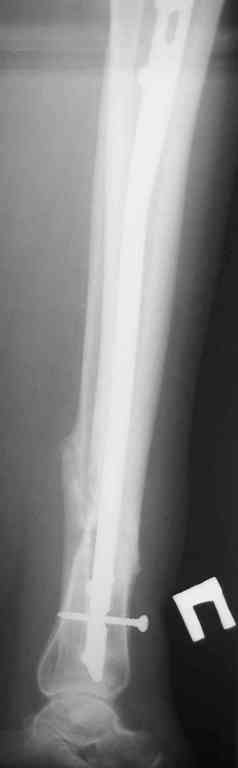

Re: Ложный сустав голени перелом штифта

Прилагаются.